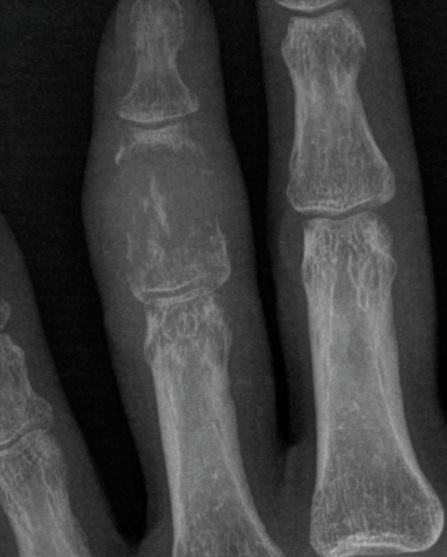

Figure 1 for case Metastatic HCC

Figure 1

Figure 2 for case Metastatic HCC

Figure 2

Metastatic HCC